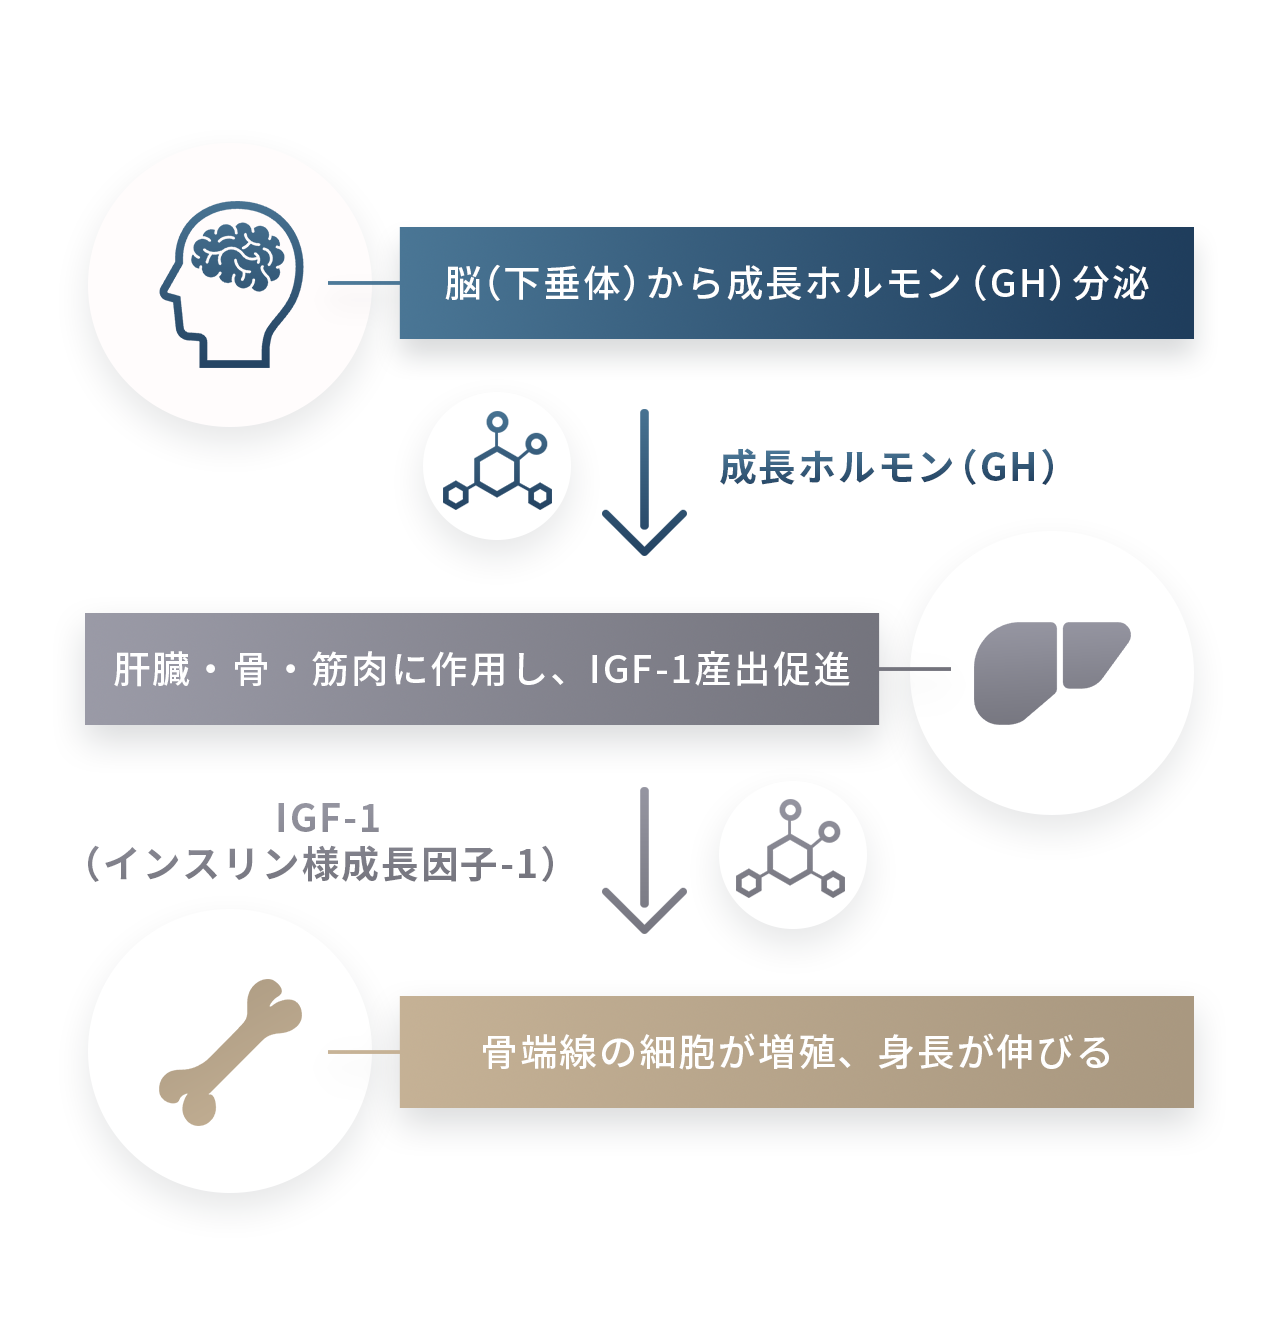

お子さまの身長は、「骨端線」と呼ばれる骨の両端に存在する軟骨組織の働きによって伸びていきます。この軟骨が細胞分裂を繰り返し、骨に変わっていくことで身長が伸びていきます。

この骨端線の働きを促進する重要なホルモンが「成長ホルモン(GH:Growth Hormone)」です。成長ホルモンは脳の下垂体から分泌され、肝臓や骨、筋肉に作用して「IGF-1(インスリン様成長因子1)」という物質を増やし、骨の成長を助けます。つまり、成長ホルモン → IGF-1 → 骨端線の細胞増殖という流れが、身長を伸ばす基本的なメカニズムです。